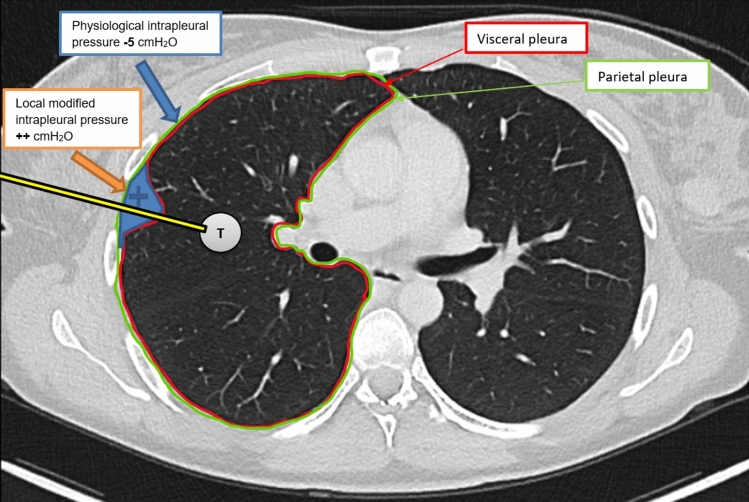

Purpose: The study aimed to evaluate whether the relative height (RH) of the entry point (EP) during CT-guided lung biopsies, adjusted for patient positioning, can predict the risk of pneumothorax during the intervention, leveraging the gravitational effects on pleural pressure.

Materials and methods: We retrospectively analyzed 128 percutaneous CT-guided lung biopsies performed at a single center between January 2018 and December 2023. Patients were grouped based on pneumothorax occurrence. Various measurement methods indirectly assessed the influence of gravitational force on pleural pressure, focusing on the RH at the EP with prone positioning adjustments (PP). Other confounding factors like patient demographics, lesion characteristics, pre-puncture fluid administration and other procedural details were assessed. Test performance metrics were compared using Chi-Square, Fisher's exact, and Mann-Whitney U tests. Univariate and binomial logistic regression assessed the influence of different parameters on pneumothorax occurrence.

Results: All measurements of lower RH at EP and pre-puncture fluid administration were significantly associated with a reduced incidence of peri-interventional pneumothorax (p < 0.01). The RH at EP adjusted for the prone position demonstrated the best predictive performance (AUC = 0.844). After adjusting for various confounding factors, both lower RH at EP adjusted for the prone position (OR 110.114, p < 0.001) and pleural fluid administration (OR 0.011, p = 0.011) remained independently associated with a lower risk of pneumothorax.

Conclusion: Strategic use of gravity by selecting the lowest possible entry point, ideally positioning the patient laterally, combined with pre-puncture pleural fluid administration, could be the key to reducing pneumothorax in CT-guided lung biopsies.